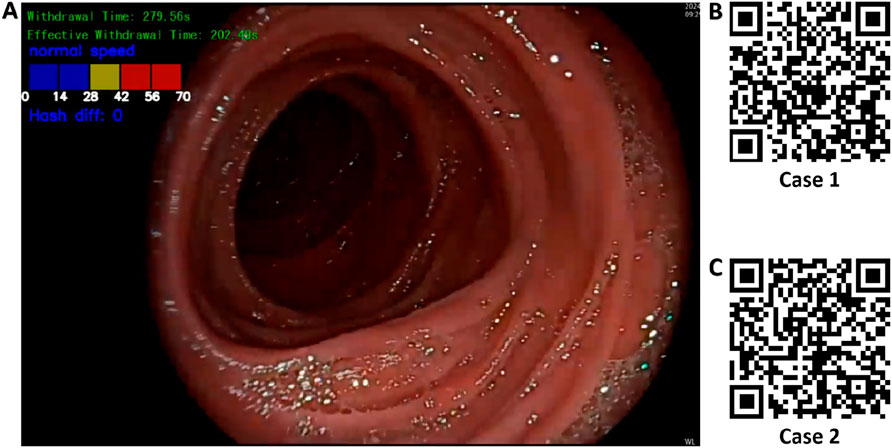

Based on the best-performing YOLOv11 m model, this study developed a multitask colonoscopy withdrawal quality control system named EWT-SpeedNet. The system integrates image classification and speed evaluation modules to achieve three core quality control functions: automatic identification and recording of WT, automated calculation of EWT, and real-time monitoring and visual display of withdrawal speed. EWT-SpeedNet supports parallel multitask processing and provides efficient, objective, and real-time feedback without the need for manual intervention. Figure 9A shows the system’s user interface, where WT, EWT, and withdrawal speed are displayed in real time in the upper-left corner of the endoscopic video.

Figure 9. Multitask AI-Based withdrawal quality control system. (A) User interface of the developed multitask AI withdrawal quality control system; (B) & (C) Two example cases demonstrating colonoscopy withdrawal procedures assisted by the system.

Case 1 (Figure 9B): During a colonoscopy procedure lasting 13 min and 35 s, once the endoscope reaches the cecum, the EWT-SpeedNet system’s WT and EWT timing modules are automatically activated. Between 5 min and 59 s and 6 min and 18 s, the patient underwent a polyp biopsy with forceps. The AI system automatically detects and subtracts the duration of this interventional procedure, enabling a more precise calculation of the EWT. Additionally, the system features an integrated visual speed scale that provides real-time feedback on withdrawal speed, helping the endoscopist maintain a controlled and appropriate withdrawal pace. With AI assistance, clinicians can focus more on mucosal observation, which may improve the detection rate of adenomatous polyps and other lesions.

Case 2 (Figure 9C): In another colonoscopy video with a total duration of 6 min and 19 s, the EWT-SpeedNet system automatically measured a WT of 2 min and 31 s and an EWT of 1 min and 55 s. During the procedure, the withdrawal speed scale repeatedly indicated in red that the withdrawal speed was in the “danger zone,” signaling that the scope was being withdrawn too quickly and that the procedure was not following standard protocols. With the support of the EWT-SpeedNet system, especially for novice or less experienced endoscopists, there is a promising potential to standardize withdrawal techniques, thereby enhancing overall examination quality and increasing the detection rate of adenomas.